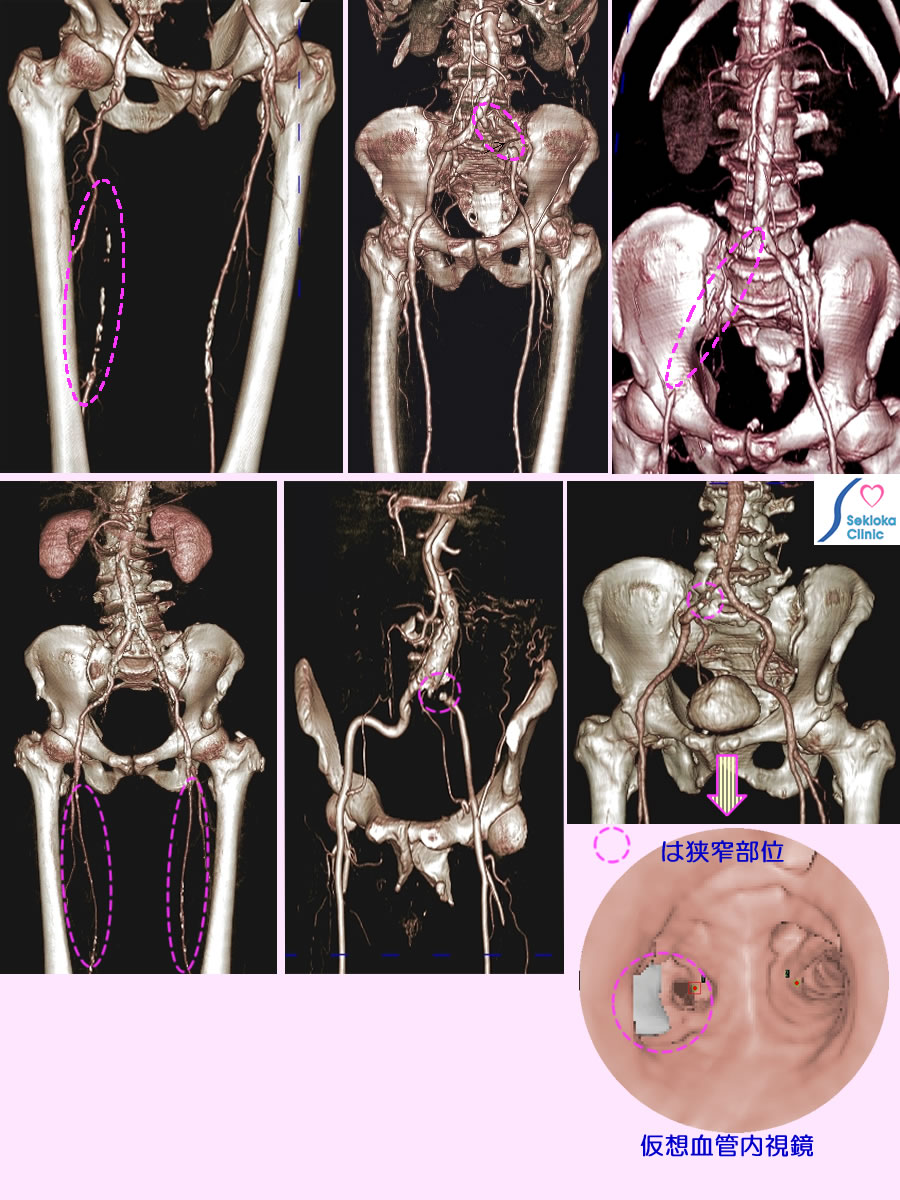

| 診断 | 足背動脈、膝か動脈、大腿動脈の触診、超音波ドプラーによる血流測定(これらは限られた部位の診断です)。血管全体を詳細に評価するには カテーテルによる血管造影。最近は造影MDCTがこれにとって代わるようになりました。添付画像は当院の症例でMDCTによる撮影です。下段右は腸骨動脈狭窄部の血管内像をわかりやすくコンピュータが可視化したものです。白い部分は石灰化(粥状動脈硬化)を表します。 |

| 治療 | 狭窄が進めば、カテーテルによる狭窄解除、ステント留置。これができない場合は 人工血管移植術。軽度また術後は抗凝固剤や血管拡張剤を服用をします。今後の進展、再狭窄を予防するため、動脈硬化の基礎要因である、高血圧、脂質異常症、糖尿病の十分な治療、禁煙などが重要です。上段中央の例は左総腸骨動脈分岐直後から完全閉塞しているためカテーテルによる再建とステント留置が行われ、上段右側の例は完全閉塞の距離が長いため人工血管移植術が行われました。上段左は大腿動脈の閉塞例です。下段中央も総腸骨動脈完全閉塞例で カテーテル治療の適応例です。下段左は大腿動脈全体が細く硬化しており薬剤治療の対象です。 |